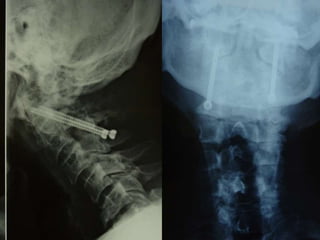

48 year old man with three week H/O severe neck pain with no improvement with

2 weeks of prednisone/narcotics/muscle relaxers

75 year old man severe neck pain

21 male severe! neck pain for three months with multiple ER

visits for narcotics/physical therapy visits/feels clumsy/ three

day history of difficulty walking following fall